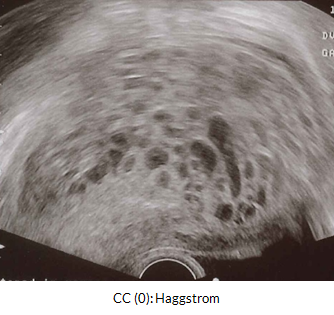

Below we have an example of a molar pregnancy with a classic snowstorm appearance on ultrasound.